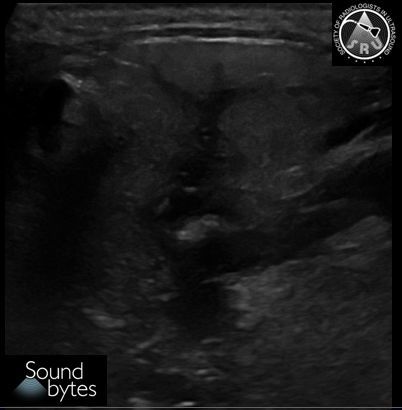

71 yo man with persistent right scrotal pain and swelling. What is your sound diagnosis?

Case courtesy of Drs. Boyan Fan and Marta Flory, Stanford University